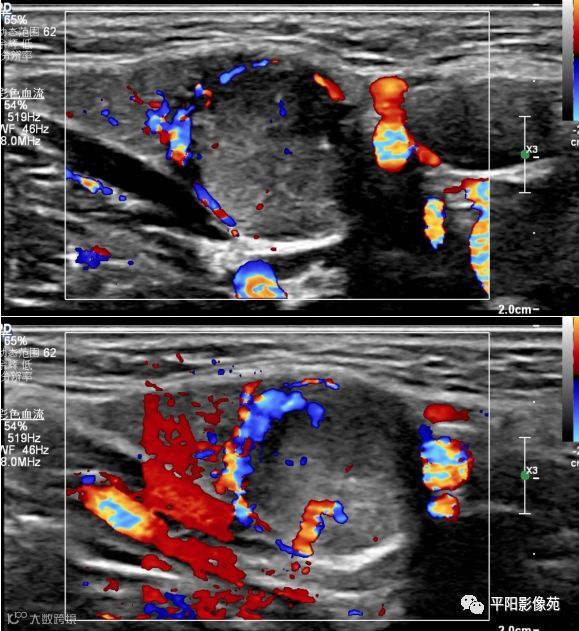

超声检查

左侧颌下腺内可见大小约1.3cm*1.2cm不均质低回声结节,内可见多发点状强回声,边界清,形态规则,CDFI:周边及内部可见血流信号。